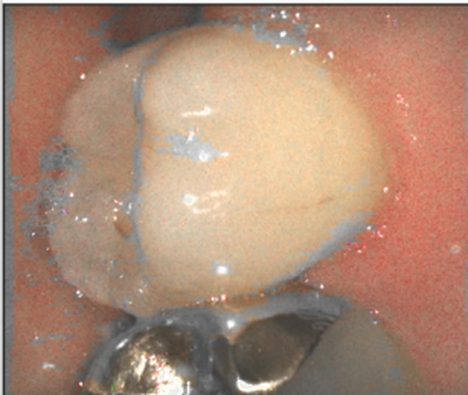

| 올바르지 않은 구강 환경 | 올바른 구강 환경 |